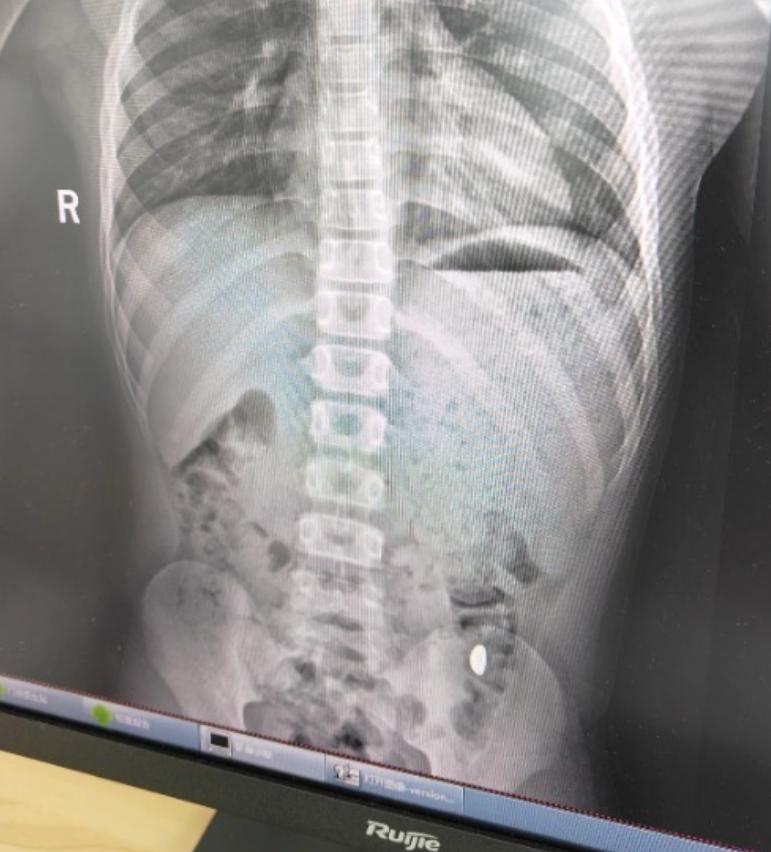

昆山市第五人民醫院門診病歷單顯示,患兒5天前誤吞約10克黃金,其間解兩次大便未發現,目前無腹痛、嘔吐等癥狀,診斷結果顯示胃內有異物。

右下加亮點為金豆。